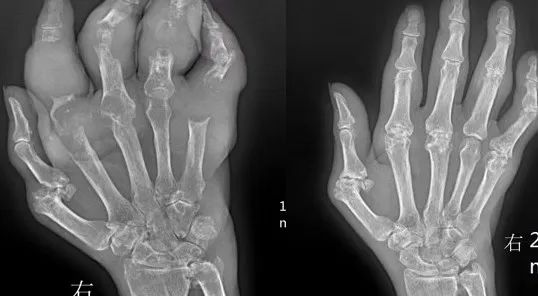

王先生是因为代谢问题,由于尿酸生成过多以及尿酸排泄很少,导致王先生的血尿酸值长期超标。王先生发生痛风后没有太过重视,以为自己只要吃了药就行了,结果王先生不仅不进行饮食控制和生活管理,就连吃药也是想起来才吃,这使得王先生痛风没几年就长出了痛风石。痛风石才出现时我建议王先生做手术清除,结果王先生还是我行我素,认为自己能控制好病情。4年时间中痛风石越长越大,几乎已经侵蚀了手部所以关节,现在想做手术也非常难,这时王先生才是真的后悔了。

在关节附近的骨骼、滑囊膜、腱鞘和软骨处的痛风石,可能会侵入骨质形成骨骼畸形,或是使骨质遭受损毁。比如发生在手足肌腱附近的结石,容易影响关节活动,并且容易引起关节急性炎症,部分巨大石或溃疡性痛风石可致关节畸形和关节物理功能严重丧失,可能会面临着截肢的风险。